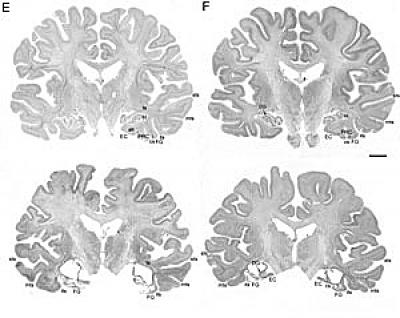

After his death, EP's brain was also processed at The Brain Observatory. The last five years have been spent parsing the data and painting a full picture of what happened to EP and why. Squire said EP's viral encephalitis infection wreaked havoc upon his brain: Large, bilateral, symmetrical lesions were found in the medial temporal lobe, portions of the brain responsible for formation of long-term memory; and whole, crucial structures were eliminated – the amygdala and hippocampus among them. Additionally, other brain regions had atrophied and white matter – the support fibers that transmit signals between brain structures – had become gliotic or scarred.